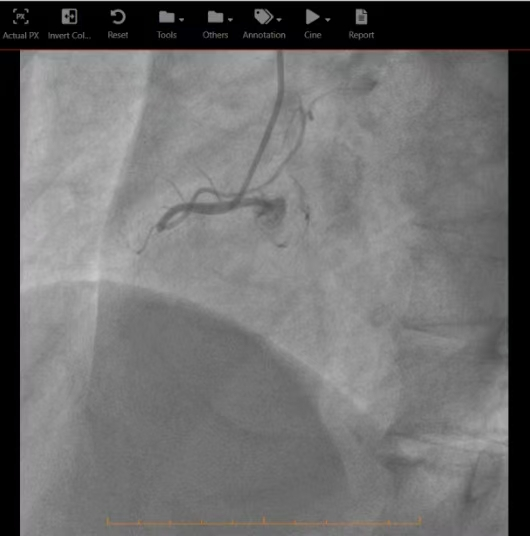

在完成必要的术前准备以及沟通后,由急诊科直接转运至心脏导管室,由心内科刘茂月副主任医师主刀,医护团队凭借娴熟的技术,快速通过导丝、球囊扩张,成功于病变处精准植入两枚药物洗脱支架,血流瞬间恢复,患者的心脏得到了及时、有效的再灌注。手术过程顺利,术后患者生命体征逐渐趋于平稳。